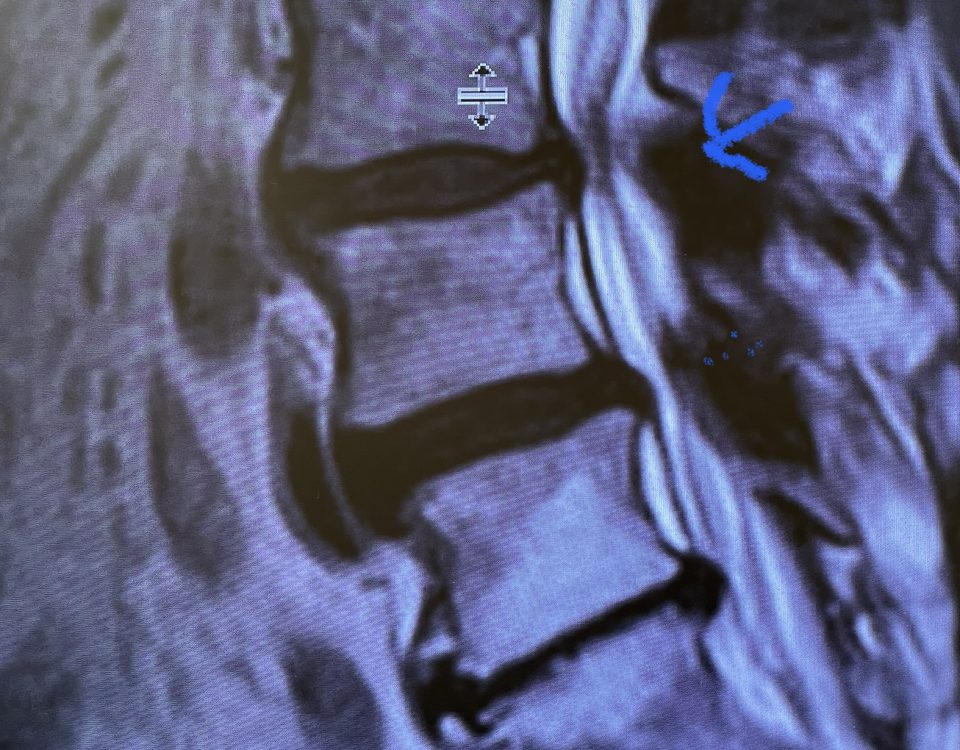

The spinal synovial cyst is one of the most interesting expressions of spinal instability. They emanate from the synovial lining of a degenerated facet joint that […]

People are obsessed with cysts! When you think about it, the body likes to form cysts. Why does this happen? Cysts can form just about anywhere […]